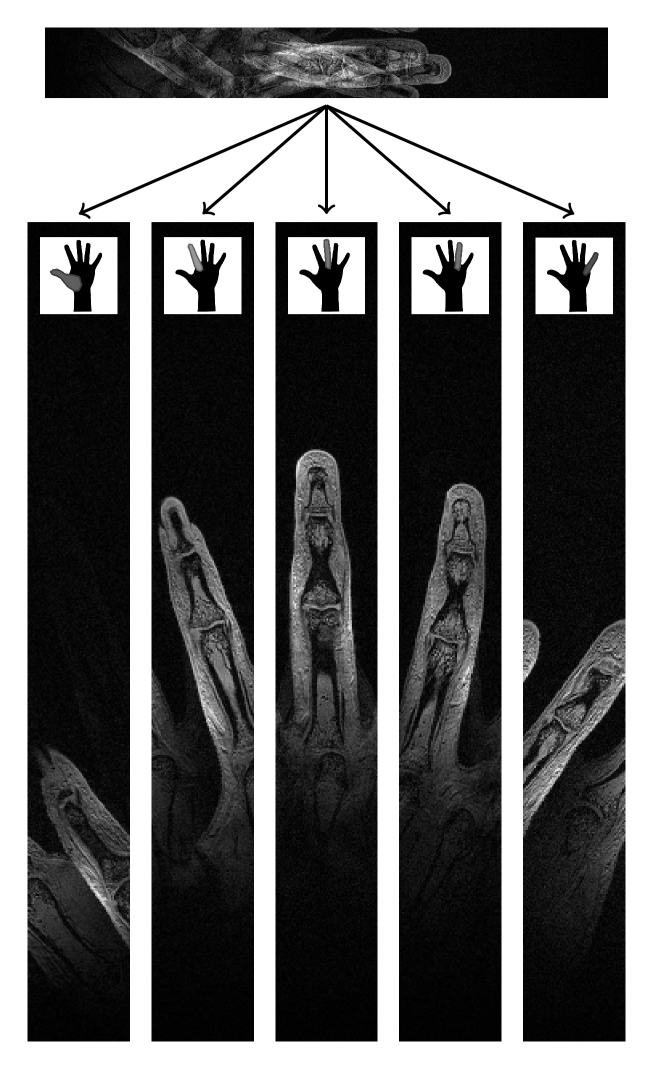

[Uncaptioned image]

Supplemental Figure 4: A 3D data set (non-selective excitation) acquired covering only the middle finger. The top panel shows a central slice from the 3D data set combining all data from all coils. Underneath the top panel, each of the individual coil images (measured simultaneously) are placed side by side to reveal the individual fingers. Note that, no parallel imaging reconstruction techniques were used to separate the images. (0.5 mm isotropic, 512x64x104 matrix, 256x32x52 mm field of view, TR = 12ms, TE = 5ms, 10 degree flip angle, total scan time 1min 20sec).